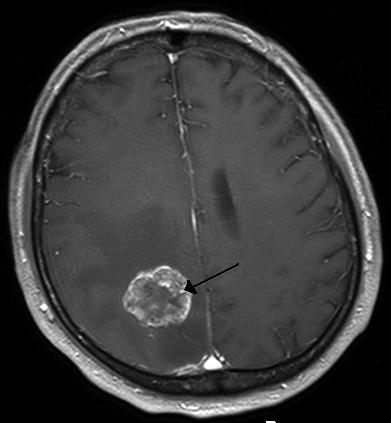

뇌종양의 정확한 원인은 밝혀져 있지 않습니다. 다만 1900년대 초, 기계충을 없애려고 머리에 방사선을 조사하였는데 뇌종양이 발생하여 뇌종양과 방사선과의 연관성이 보고된 정도입니다. 환자나 보호자가 많이 물어보는 것 중 하나가 유전되거나 전염이 되는가 하는 점입니다. 신경섬유종증과 같은 일부 뇌종양에서 유전성 경향을 보이기는 하나, 대부분은 유전되지 않고 전염되지도 않는 병입니다.